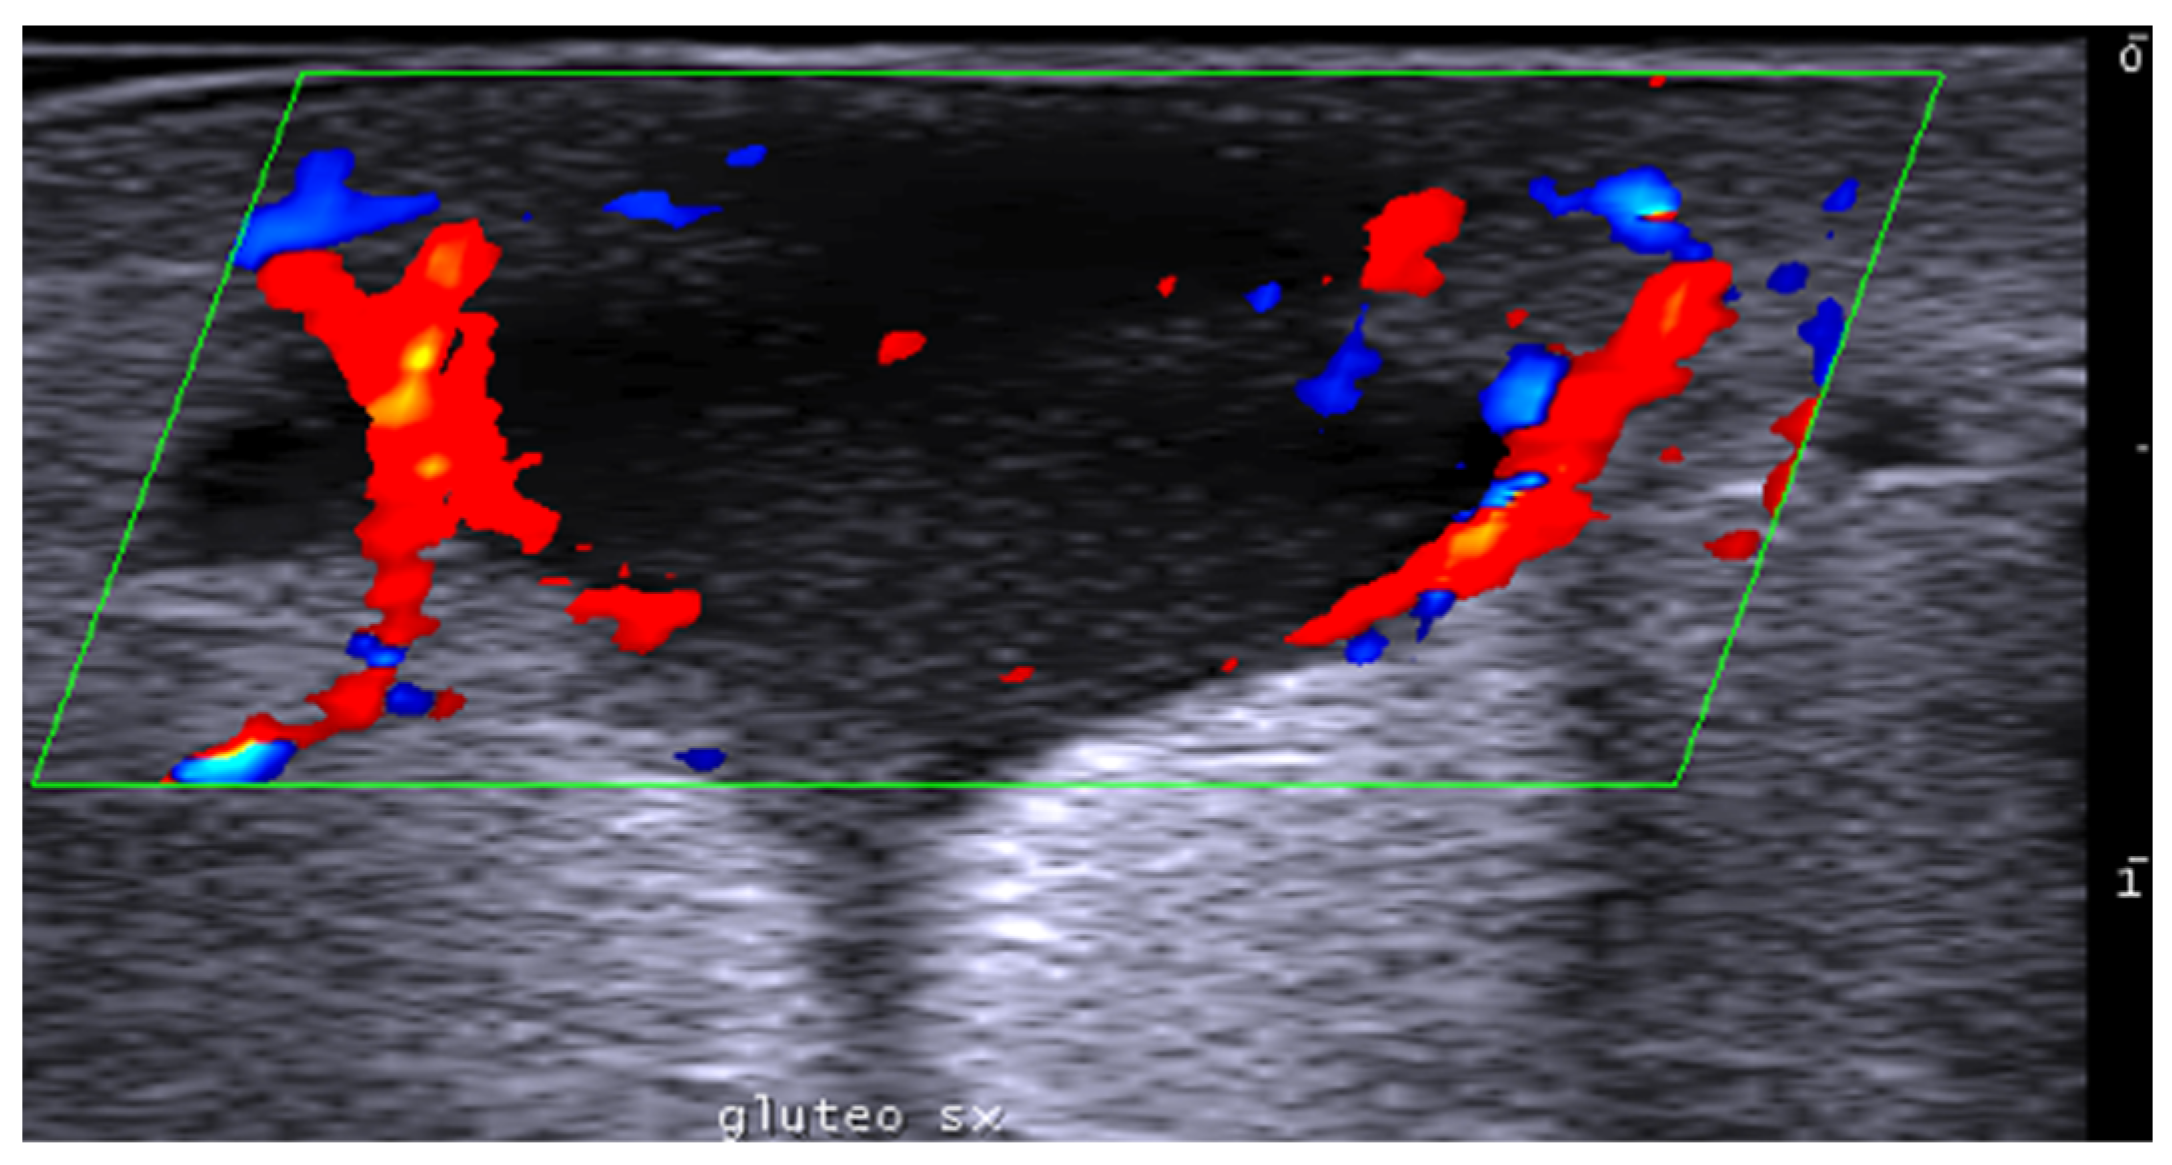

- Del Vecchio, D.; Kenkel, J.M. Practice Advisory on Gluteal Fat Grafting. Aesthetic Surg. J. 2022, 42, 1019–1029. [Google Scholar] [CrossRef]

- Vidal-Laureano, N.; Huerta, C.T.; Perez, E.A.; Earle, S.A. Augmented Safety Profile of Ultrasound-Guided Gluteal Fat Transfer: Retrospective Study with 1815 Patients. Aesthetic Surg. J. 2024, 44, NP263–NP270. [Google Scholar] [CrossRef] [PubMed]

- Elsaftawy, A.; Ostrowski, P.; Bonczar, M.; Stolarski, M.; Gabryszuk, K.; Bonczar, T. Buttock Augmentation with Ultrasonic Liposuction and Ultrasound-Guided Fat Grafting: A Retrospective Analysis Based on 185 Patients. J. Clin. Med. 2024, 13, 1526. [Google Scholar] [CrossRef]

- Elsaftawy, A.; Ostrowski, P.; Bonczar, M.; Stolarski, M.; Gabryszuk, K.; Bonczar, T. Enhancing Buttock Contours: A Safer Approach to Gluteal Augmentation with Ultrasonic Liposuction, Submuscular Implants, and Ultrasound-Guided Fat Grafting. J. Clin. Med. 2024, 13, 2856. [Google Scholar] [CrossRef]

- Wang, B.; He, P.; Zhao, R. B-ultrasound-assisted gluteal fat grafting in Asians: A prospective study of quantitative results from three-dimensional imaging and B-ultrasound analysis. J. Plast. Reconstr. Aesthetic Surg. 2024, 94, 12–19. [Google Scholar] [CrossRef] [PubMed]

- Durán Vega, H.C.; Manzaneda, R.; Flores, E.; Manfrim, C.; Morelli, H. Deep Back Liposuction: Ultrasound-Guided Deep Fat Liposuction of the Subiliac Crest. Aesthetic Surg. J. 2024, 44, 296–301. [Google Scholar] [CrossRef]